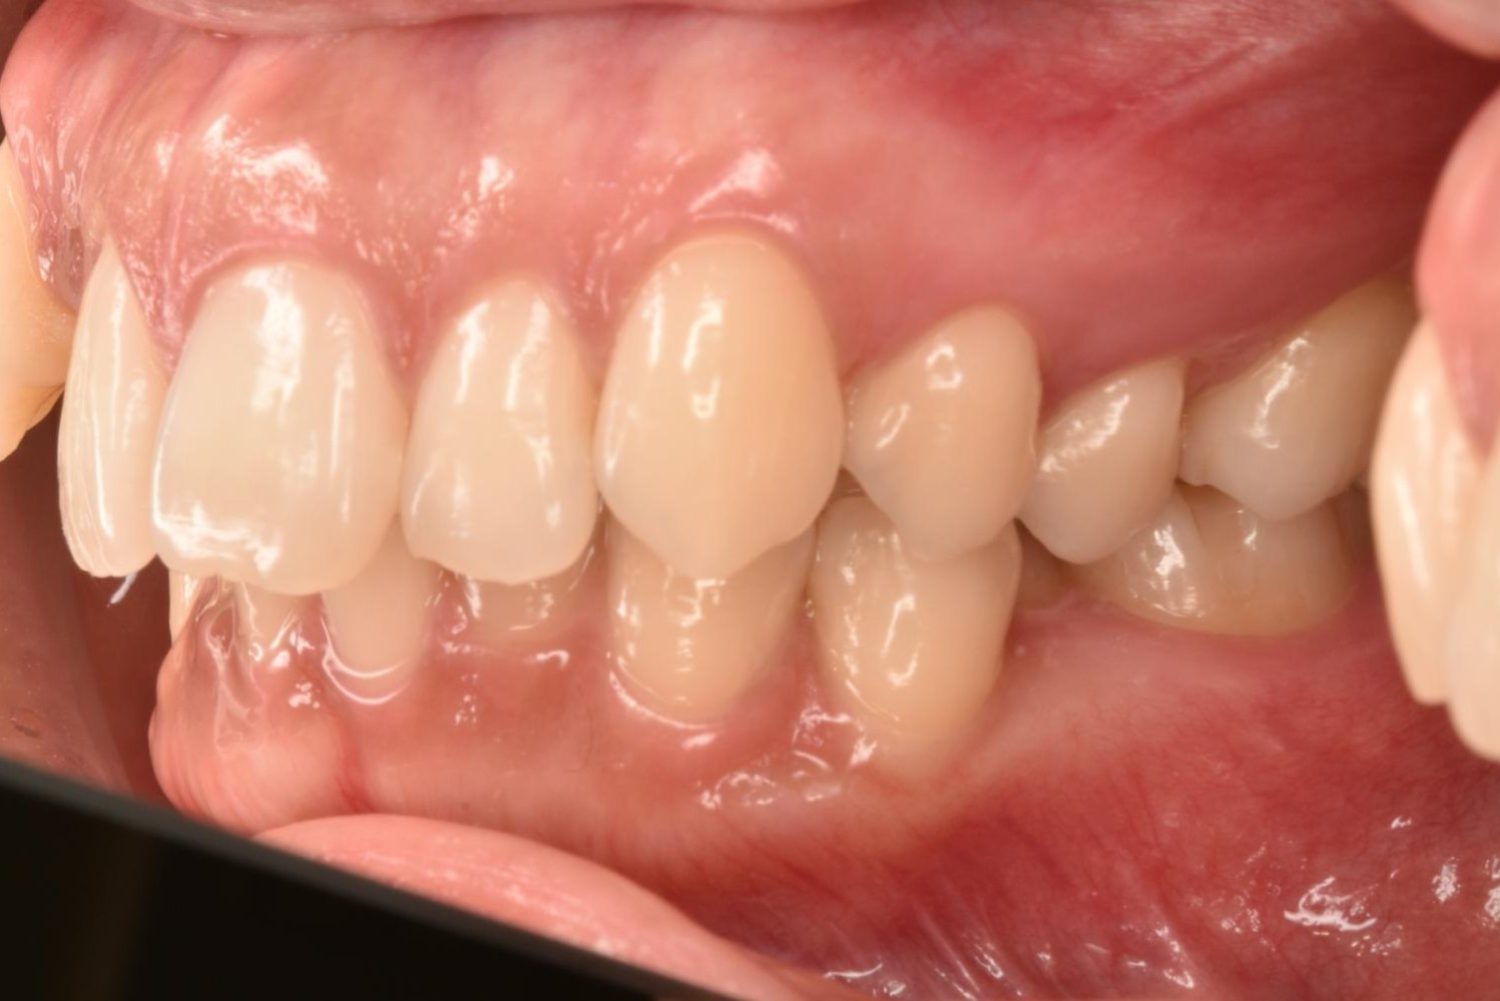

| 主訴 | 20代女性の患者さん。右上の八重歯が突出しており、前歯の見た目にコンプレックスを抱いていた。下顎の左右第2小臼歯(5番)が舌側に大きく傾斜しており、食事の際に、食べかすが詰まりやすく日常的に不快感を覚えていた。噛み合わせの改善と、見た目のバランスを整えたいという希望があり、矯正治療を行うことになった。また、目立ちにくい方法で治療を進めたいという意向から、マウスピース型装置の矯正 “インビザライン”を希望。 |

| 治療内容 | 下顎の左右第2小臼歯(5番)は舌側に大きく傾斜しており、矯正治療における歯の移動効率や全体の歯列バランスを考慮し、便宜抜歯を行った。また、上顎の左右第1小臼歯(4番)についてもスペース確保の目的で抜歯を実施し、全顎的な歯列の配列を円滑に進められるよう計画。矯正装置は、患者さんのなるべく目立ちにくい治療を行いたいという強い希望とライフスタイルに合わせて、マウスピース型矯正装置「インビザライン」(※1)を採用。抜歯が必要となる矯正治療は、診断・治療の難易度が高い方法である。当院ではCTやセファログラムなどの先進的な設備を完備し、多角的な診査診断と豊富な臨床経験をもつ理事長による治療を行うことで、このような難症例にも対応可能。 また、当院は矯正治療だけでなく、むし歯治療やクリーニングなどの一般歯科・予防治療も一貫して管理する包括的な審美治療を行う総合クリニック。治療中にむし歯などの問題が見つかっても、すぐに対応できるため、患者さんの通院の負担をできる限り抑えたスムーズな対応が可能。矯正専門医院ではできない包括的なサポート体制こそが、シャングリラデンタル横浜歯科矯正歯科で矯正治療を受けるメリットである。 矯正治療中は定期検診で経過の確認とクリーニングを行い、必要に応じて治療計画の見直しやマウスピース型装置の追加を行った。患者さんの高い装着遵守率も相まって、歯列は順調に整い、機能的にも審美的にも良好な結果をえることができた。 (※1)未承認医薬品等であるため医薬品副作用被害救済制度の対象とはならない可能性があります。 |